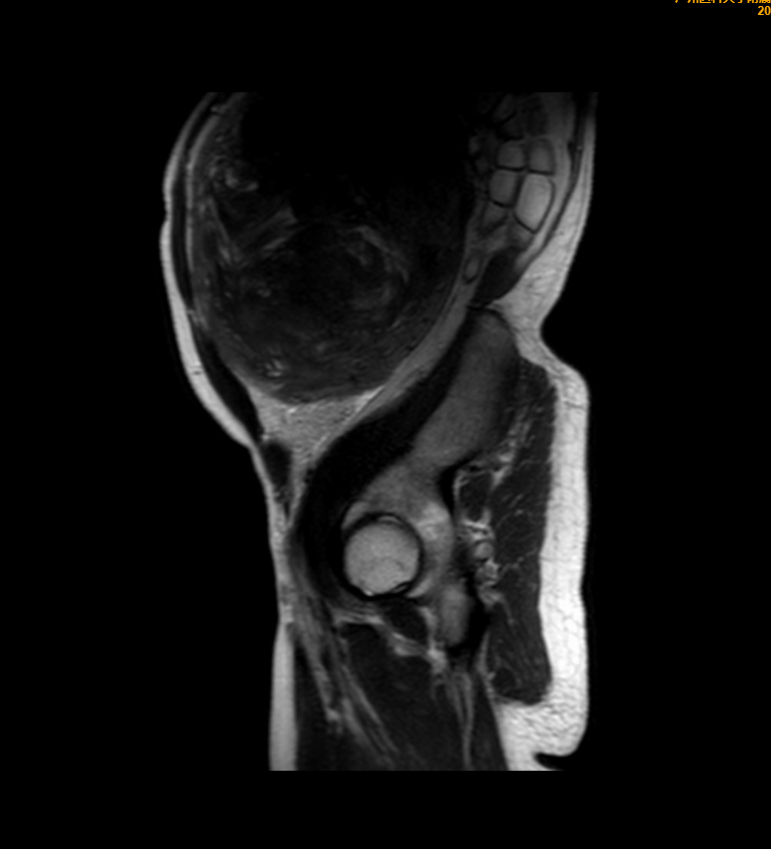

王女士术前影像检查

这个“巨无霸”肌瘤血管极其丰富,稍有不慎就可能大出血;此外,巨大的肌瘤紧紧压迫着周围的肠道、输尿管,分离时容易造成损伤。但若再放任肌瘤继续生长,可能会出现因经量增多、经期延长而严重贫血,也有可能出现肿瘤压迫症状如尿频、便秘等,甚至有恶变风险。

经过详细的术前评估和充分准备后,广医三院妇科、麻醉科、手术室团队默契配合,为王女士实施了开腹全子宫切除术,切下来的子宫约莫有一个“篮球”那么大,重达4公斤!